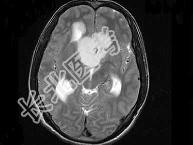

- 单项选择题男,32岁, 头痛,头昏半年, 加重10天伴抽搐,根据所提供图像, 最可能的诊断是 ( )

A、胶质瘤

B、颅咽管瘤

C、蛛网膜囊肿

D、表皮样囊肿

E、胆脂瘤